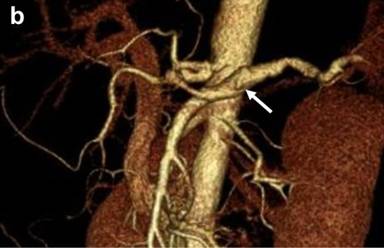

Bleeding from the papilla of Vater was not evident with upper gastrointestinal endoscopy on the day of admission. Conservative treatment was performed for the acute pancreatitis because the patient was hemodynamically stable. The epigastric pain and the serum amylase level improved after conservative treatment. During hospitalization, however, the patient developed the same epigastric pain as that usually experienced before melena, and the serum amylase level was found to be 243 U/L. We performed emergency upper gastrointestinal endoscopy to confirm the diagnosis of hemosuccus pancreaticus. Bloody pancreatic juice was observed exuding from the papilla of Vater (Figure 2). We concluded that the recurrent episodes of epigastric pain and melena had been caused by hemosuccus pancreaticus. There were no clinical or laboratory findings suggestive of arteriosclerosis or vasculitis, and diagnostic imaging showed no evidence of chronic pancreatitis or pancreatic pseudocyst. We therefore considered that the splenic aneurysm was due to segmental arterial mediolysis. We planned transcatheter arterial coil embolization for the splenic aneurysm, and the patient was discharged. However, he was re-admitted before the scheduled embolization because of sudden epigastric pain and, when tested, his serum amylase level was found to be 631 U/L. CECT revealed leakage of contrast medium into the main pancreatic duct from the aneurysm, along with dilatation of the upstream main pancreatic duct (Figure 3ab).

An emergency intervention was then carried out. Angiography clearly revealed a fusiform aneurysm of the middle-distal splenic artery and narrowing of the proximal splenic artery (Figure 4a). All parts of the splenic artery were successfully coil-embolized (Figure 4b). Twenty days later, intervention for dissection of the celiac artery was performed. The celiac artery including the false lumen was successfully coil-embolized (Figure 4c). The patient has since shown no recurrence of the epigastric pain or melena.

Figure 4. a. Angiography of the celiac artery clearly showing the narrowing of the proximal splenic artery (small arrow) and a fusiform aneurysm of the middle-distal splenic artery (large arrow). b. Angiography of the celiac artery showing that all parts of the splenic artery were successfully coil-embolized. c. Lateral angiography of the celiac artery showing that the celiac artery including the false lumen was successfully coil-embolized. |